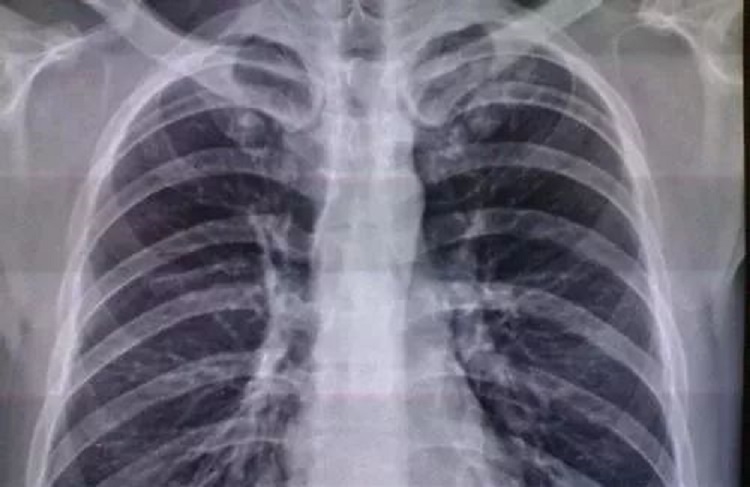

1、医学影像学

在最新的医学类专业排名中,医学影像学跃居榜首。其实也不难理解,近年来,电子设备的不断发展使得医学影像技术越来越先进,不同科室不同病种的病人进入医院以后不可避免地都要走医学影像的流程,借助医学影像完成病情的诊断。所以医学影像学专业的兴起是必然的。更重要的是,医学影像类专业的薪资较高,但是工作又比较轻松,属于很受欢迎的医学类工作。